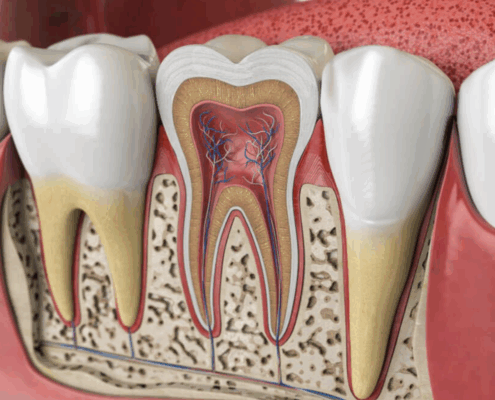

Résection apicale ou APICOECTOMIE